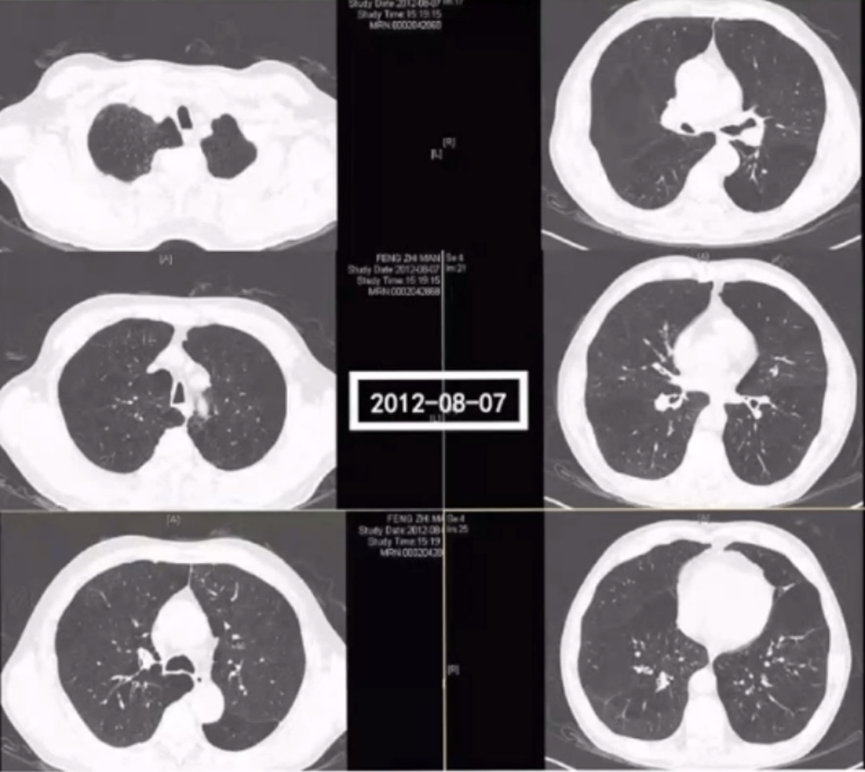

年轻女性,37岁,在家中收拾发霉的玉米杆时出现哮喘急性发作。急诊胸片可见双肺过度通气状态,右上肺明显不张。因呼吸衰竭插管,由于气道阻力非常高,插管后出现了明显的气压伤,此时已出现纵隔气肿和皮下气肿。单纯依靠呼吸机维持较为困难,只能通过血滤稳定pH。多次痰培养出现烟曲霉,给予两性霉素B联合伏立康唑,同时维持其脏器功能。

从影像学分析,初始患者气道内病变并不多,随着疾病进展,气道内和肺实质内可以见斑片状沿支气管血管束分布的结节/斑片影,在气压伤严重阶段,肺内渗出影亦明显增加。但随感染进展,双下肺右肺门靠外处的斑片影/团片较明显,这也说明局部感染从气道向肺实质的播散。最终由于抗真菌治疗有效,经过1个月左右的救治,患者呼吸功能逐步恢复,肺内影像学逐渐稳定和好转。

下图为患者病程中的胸部CT,左侧可见大量结节、斑片影,右侧所示为抗感染治疗后,结节、斑片影明显吸收。

图片